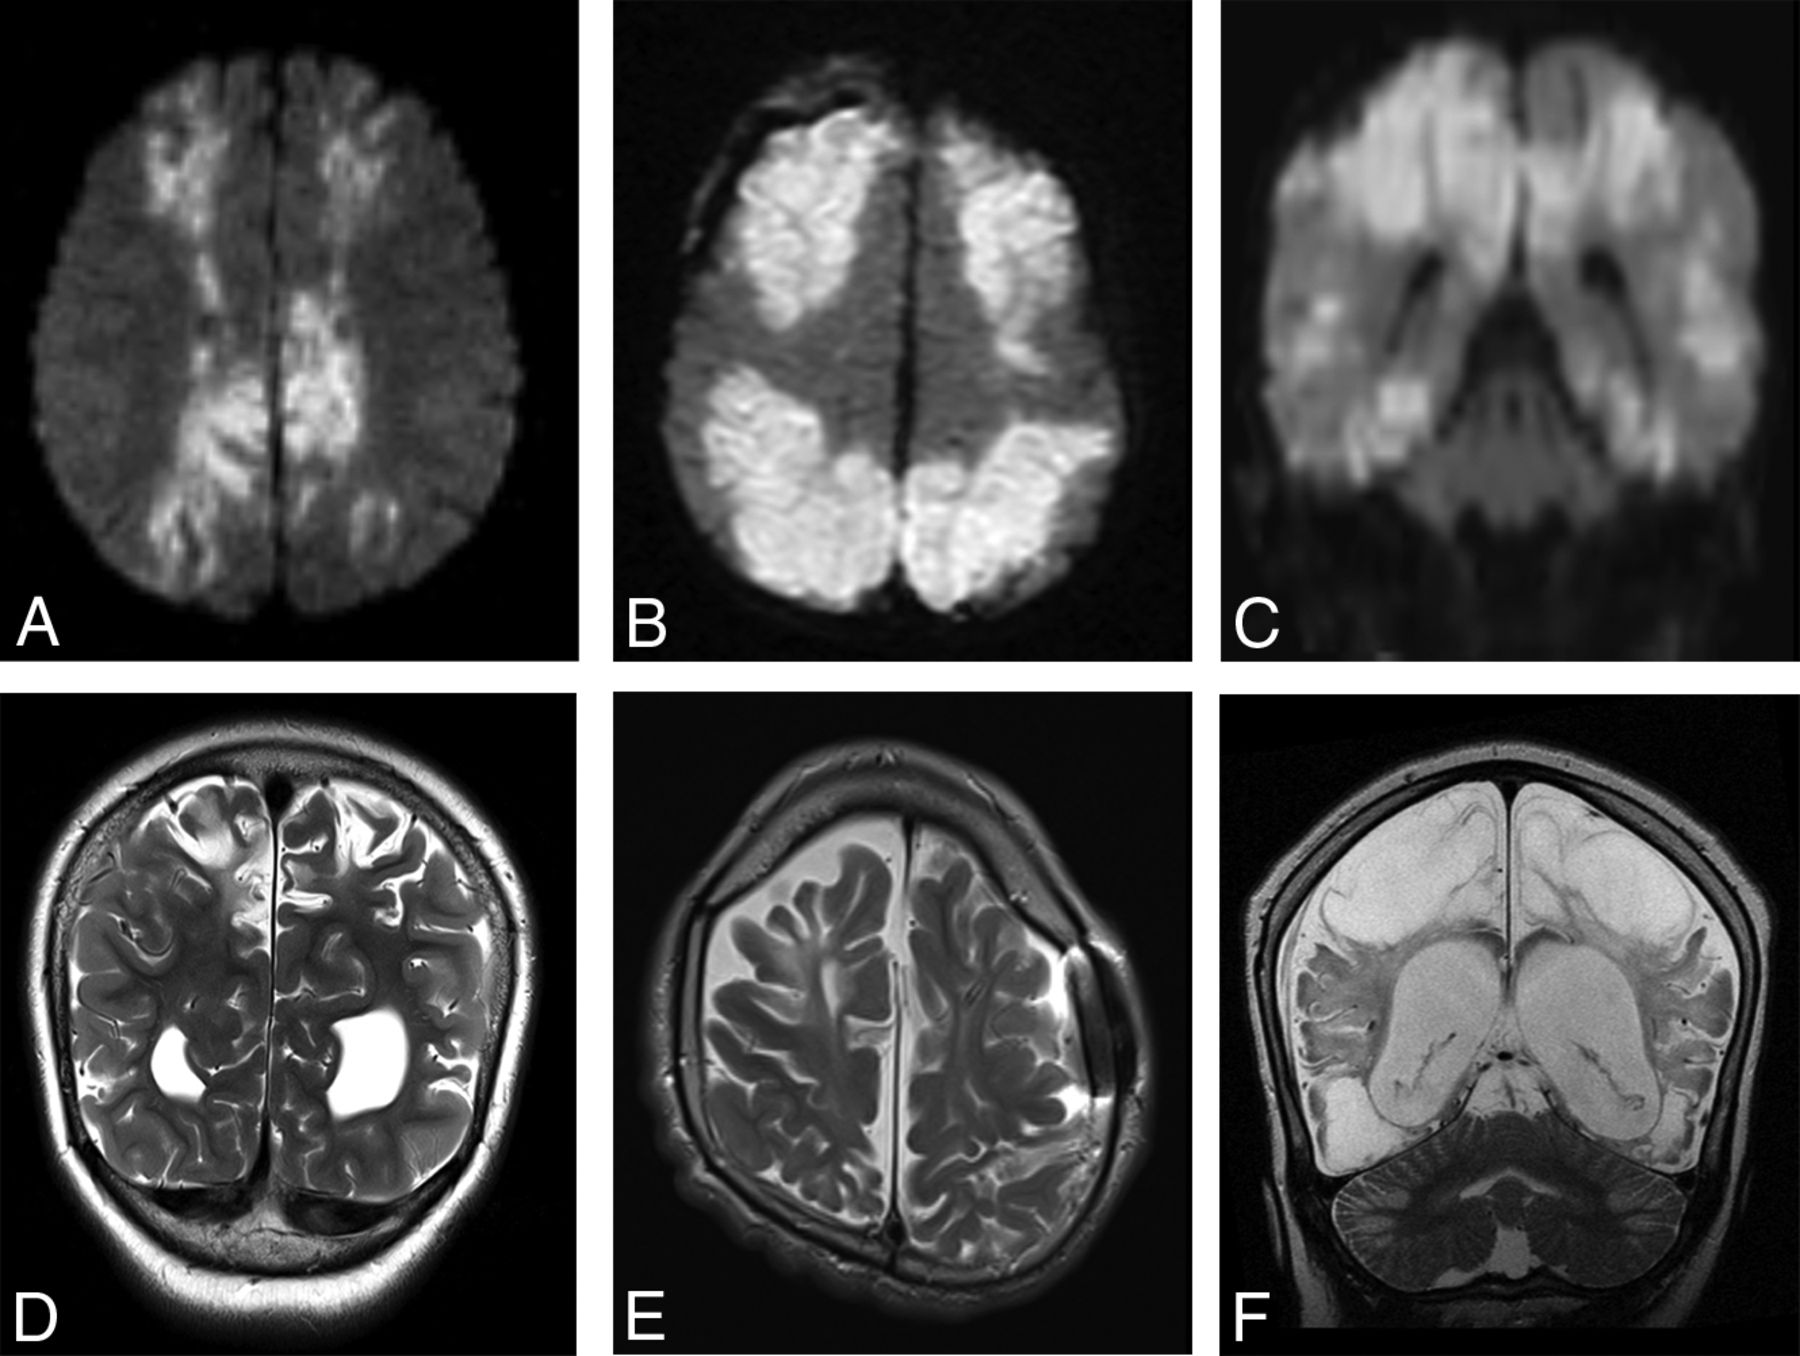

In the supratentorial brain, 87% (20/23) of patients demonstrated a classic parasagittal watershed pattern of cortical injury (Fig 7), with 11 with additional evidence of associated basal ganglia injury. Seventeen patients had watershed infarctions and a concordant clinical history of HII. The remaining 3 patients demonstrated a watershed pattern of injury typical of PRES. In all cases, the apparent timing of the supratentorial injury was consistent with the estimated timing relative to the suspected clinical event.

Findings of both acute and remote supratentorial watershed injury in patients 1–6 (A–F, respectively). Acute watershed infarcts with signal abnormality on axial (A and B) and coronal (C) DWI in a characteristic parasagittal distribution. Subacute or remote watershed infarcts with hyperintensity and parenchymal volume loss on coronal (D and F) and axial (E) T2.